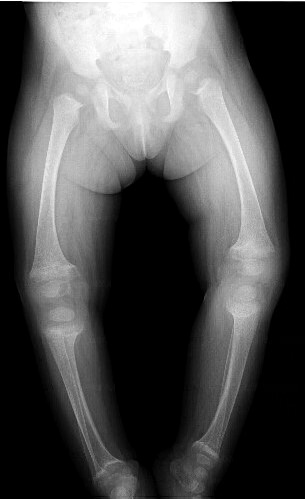

En la radiografía de extremidades se describía un ensanchamiento de las metáfisis femorales y tibiales con pérdida de nitidez y aspecto "desflecado" compatible con raquitismo (Figura 1).

Con diagnóstico de Raquitismo carencial se administró como tratamiento inicial vitamina D a dosis de 4.000 UI / diarias vía oral. En el control radiográfico posterior a los 4 meses de iniciado el tratamiento se apreció mejoría de las alteraciones óseas, así como una resolución de las alteraciones del metabolismo del calcio y fósforo.